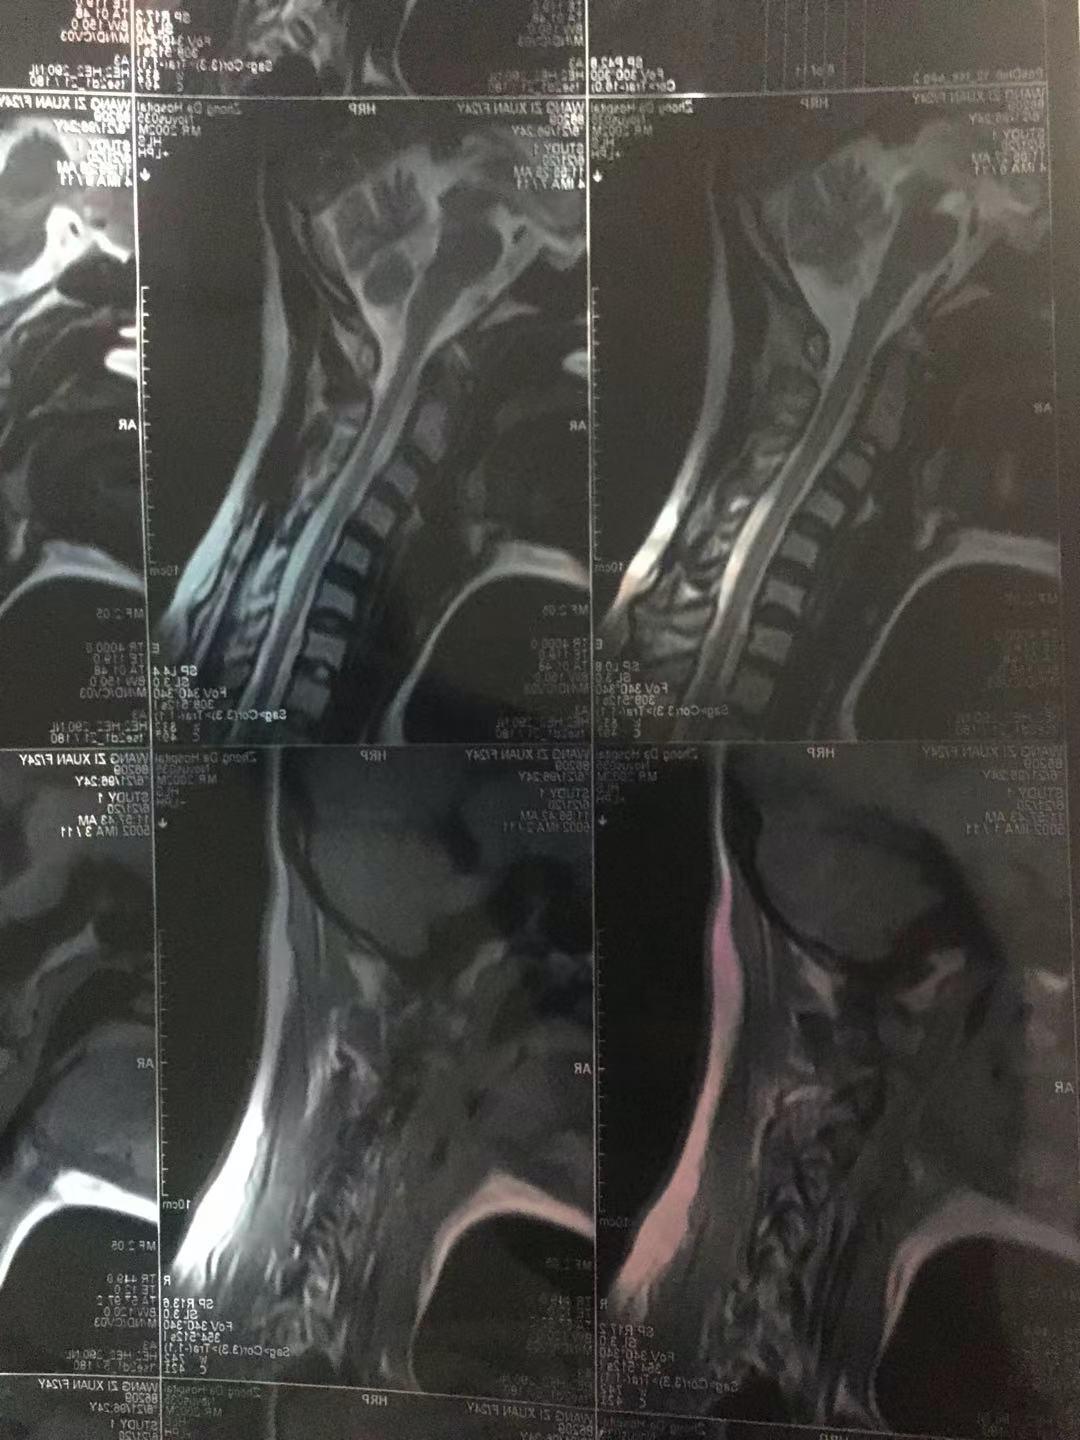

因为骨骼歪曲,动不好有时就会压迫神经,呆在壳子中的塑形,令我伏案学习时脖子过度前倾,如今离开它后出现了颈椎不适,严重时出现手麻脚麻。劳动稍对姿势不利,就会腰痛到睡不着觉。

图片来源:作者提供虽然脱离了矫正的「硬性」时段,但和「脊柱侧弯」这种疾病的斗争的「软时段」却远远没有结束。